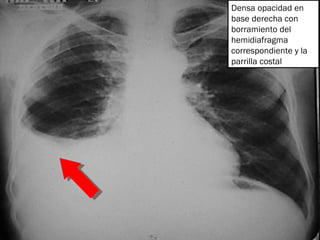

Densa opacidad en base derecha con borramiento del hemidiafragma correspondiente y la parrilla costal